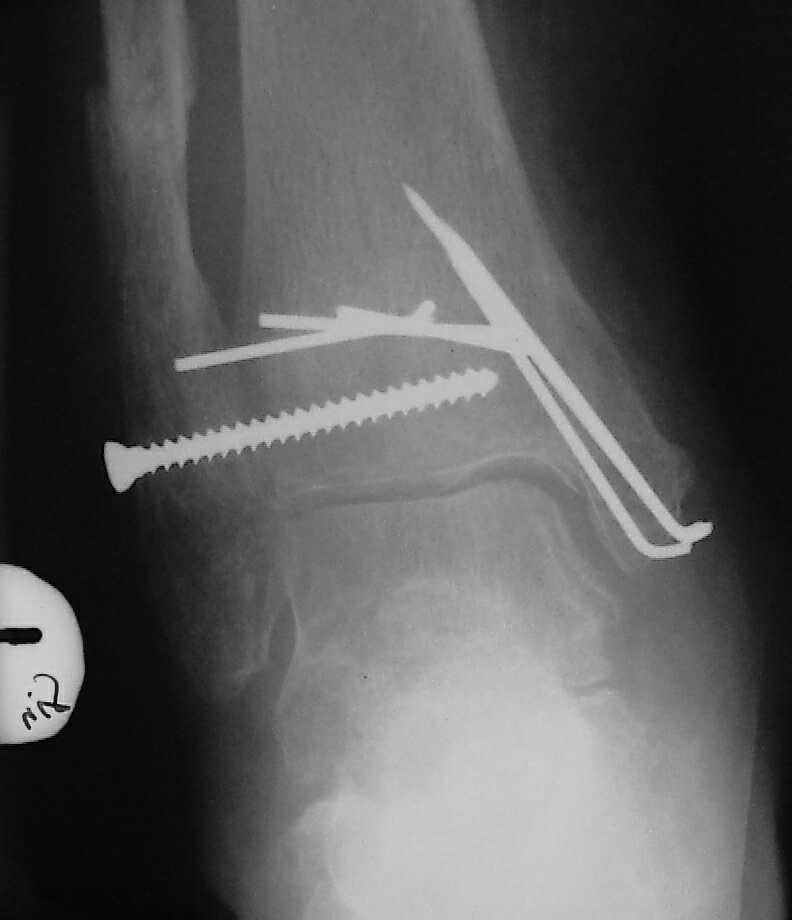

Ретроспективно, на Ваш взгляд, что изменилось бы при остеосинтезе более массивными имплантами?(выбор в пользу спиц как раз и был из-за минимального объема оставляемых имплантов) Иммобилизация 7 недель это очень длительно? Результат на 4 RTG - в чем нефункциональность? - согласен, что репозиция заднего края не была достигнута. Какие признаки ложного сустава мед. лодыжки ?

Уважаемый Владимир. Нестабильность и нефункциональность, как мне видится по снимочкам, была изначально,об этом ниже В чём вы видите массивность третьтрубчатой, например титановой 1.5 мм пластины? Ими оперируют во всём мире и получают хорошие результаты, а почему у нас это массивно мне непонятно.Спицевая "тюрьма" хороший способ, но только для временной интраоперационной фиксации, хотя лично я редко пользуюсь, на то есть костодержатели для малых фрагментов и репонирующие винты. Кстати в данном случае, при её остеопорозе лучше было бы поставить LCP (опуская финансовую сторону вопроса, в теории). А вот функциональность - при правильном подборе и установке металлоконструкций пациент нуждается в иммобилизации на срок заживления швов, а уж потом ходьба без нагрузки на оперированную конечность 6 недель - (базовый курс АО). Ретроспективно, как мне видится, при хорошей репозиции и фиксации всё бы консолидировалось, хотя на всё воля божья, но по крайней мере не нужно было бы удалять железки. Иногда ставишь всё как мама родила, а потом очень плохие последствия. Признаки ложного (?) я вижу на снимках,хотя это может быть и банальное отсутствие консолидации за столь длительный срок, что само по себе я бы расценил как ложный сустав. А что Вы сами думаете по этому поводу? И как планируете артродезировать? (если планируете). Мне кажется, самое обидное то, что и эндопротез голеностопного поставить там просто некуда. Я бы думал об очень сомнительном прогнозе.

На остеомиелит/гнойный артрит не очень похоже, больше на трофические расстройства. Попробовать бы что-то из нестероидных противовоспалительных. Конечно, еще и на фоне коррекции гликемии.

По стихании обострения - артродез голеностопного сустава был бы окончательной операций, обеспечивающей опорную и безболезненную конечность. Мы бы сделали L-образным доступом параллельно переднему контуру наружной лодыжки с уходом кзади, с пересечением малоберцовой кости вверху раны и отворотом единого кожно-костного лоскута, с последующей продольной остеотомией малоберцовой кости для обнажения губчатой кости; такой доступ дает очень хороший обзор суставных поверхностей таранной и большеберцовой костей для сятия хрящевого покрова. Фиксация аппаратом из двух опор - по паре спиц в таранной и

большеберцовой костях, наружную лодыжку прижать спицей с упором (лучше в виде петли) к продольному пазу, сформированному по латеральной поверхности сочленяющихся костей.